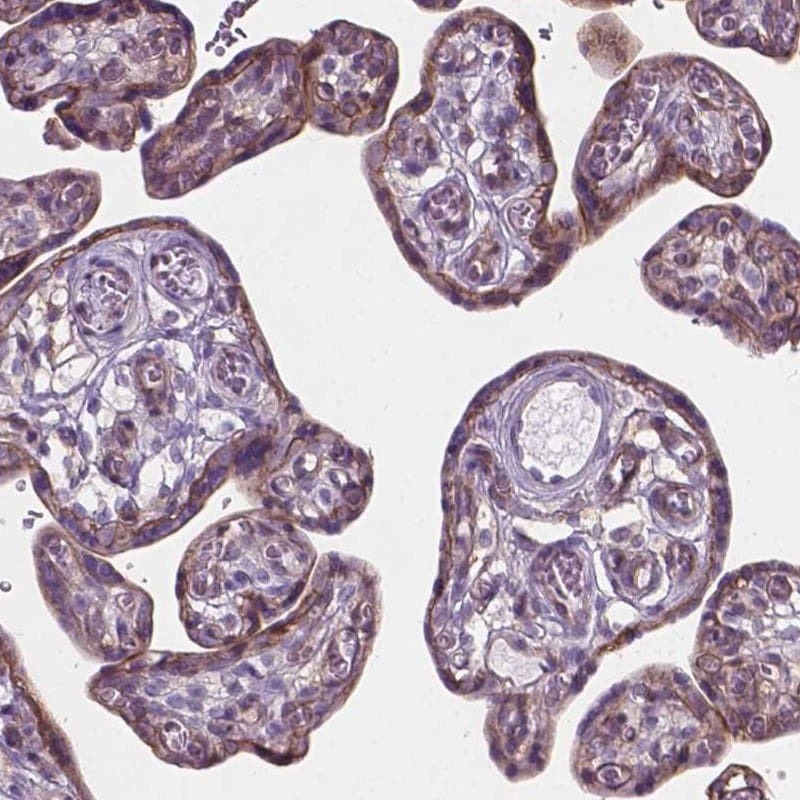

Supportive validation

- Submitted by

- Invitrogen Antibodies (provider)

- Main image

- Experimental details

- Immunohistochemical staining of KIAA0040 in human placenta using a KIAA0040 Polyclonal Antibody (Product # PA5-64386) shows cytoplasmic positivity in trophoblasts.